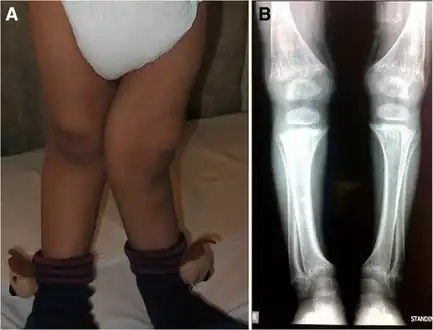

There (are) three distinct types of cystinosis each with slightly different symptoms: nephropathic cystinosis, intermediate cystinosis, and non-nephropathic or ocular cystinosis. Infants affected by nephropathic cystinosis initially exhibit poor growth and particular kidney problems (sometimes called renal Fanconi syndrome). The kidney problems lead to the loss of important minerals, salts, fluids, and other nutrients. The loss of nutrients not only impairs growth, but may result in soft, bowed bones (hypophosphatemic rickets), especially in the legs. The nutrient imbalances in the body lead to increased urination, thirst, dehydration, and abnormally acidic blood (acidosis).

Rickets in cystinosis. a- A cystinosis child with evident rachitic bone deformities. b- Active rachitic bone disease in X-Rays -